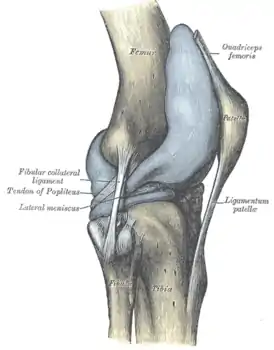

![]() Правый коленный сустав, сбоку. | |

В передней части сустава расположен надколенник (коленная чашечка). Надколенник и четырёхглавая мышца бедра соединены сухожилием, продолжением которого является связка надколенника. В связочный аппарат входят:

- боковые (малоберцовая и большеберцовая коллатеральные)

- задние (подколенная, дугообразная, связка надколенника, медиальная и латеральная поддерживающие)

- внутрисуставные (крестообразные, поперечная связка колена (между менисками)

Является сложным (несколько суставных поверхностей), комплексным (содержит мениски). По форме является мыщелковым.

У человека коленное сочленение допускает движения сгибания и разгибания (фронтальная ось) — общий объём движений 151 градусов, а при согнутом положении (вследствие расслабления коллатеральных связок) — и вращение вокруг оси. Общий объём вращений составляет 15 градусов, пассивное вращение — 35 градусов. Связки играют роль ограничения движений сустава.